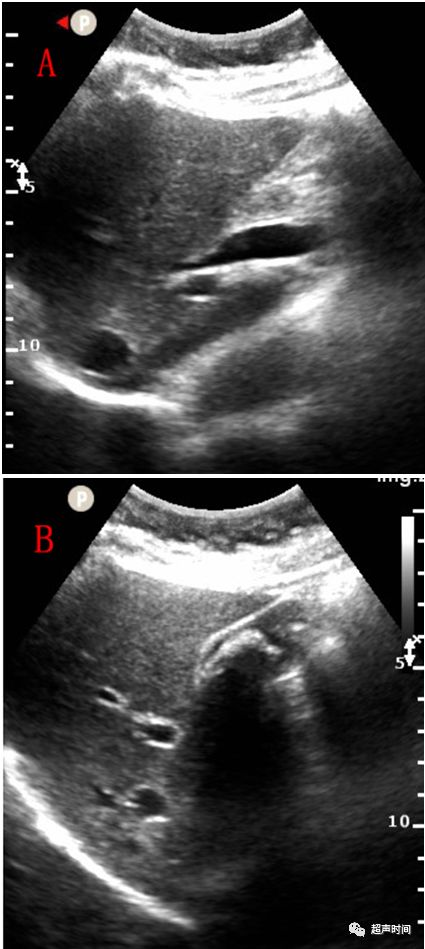

术后 1 月患者空腹行门诊超声复查,发现胆囊窝处探及疑似「胆囊」轮廓(图 2),肝门处胆管轻度扩张(图 3)。在多次核对患者信息及查看患者住院病历后请上级医师会诊,嘱患者食两个油煎鸡蛋 30 分钟后再次检查,发现胆囊窝处未见异常,肝门处胆管未见扩张(图 4)。

图 4 患者食用两个油煎鸡蛋 30 分钟后再次检查:多切面示第一次检查时发现的胆囊窝处「胆囊」大小较空腹时未见明显改变,其轮廓回声连续中断(红色箭头),多次变换体位和加压探头后均未见「胆囊」内回声变化,考虑所谓「胆囊」回声实际为肝组织;肝门处胆管内径缩小至正常(白色箭头)。PV:门静脉

在此病例中,通过临床信息和询问病史了解到患者 1 月前胆囊完整切除,术中使用夹子为生物夹(中等回声)。在自己没有足够证据判定时选择会诊上级医师,多切面示第一次检查时发现的胆囊窝处「胆囊」轮廓回声连续中断(图 4),在患者多次变换体位或加压探头后未见「胆囊」内回声变化。嘱患者食两个油煎鸡蛋 30 分钟后再次检查「胆囊」大小较空腹时未见明显改变,肝门处胆管内径缩小至正常(图 4)。此病例的「胆囊」轮廓回声可能为韧带回声,「胆囊」为肝组织。